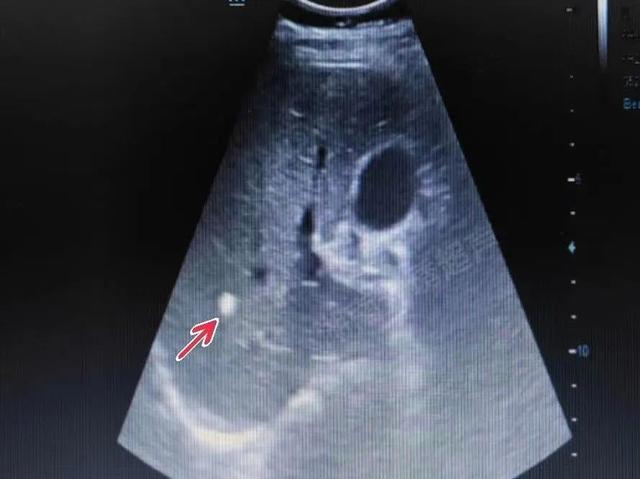

超声下肝内钙化灶典型的特征表现为:肝实质内斑点状、团块状强回声,无肝内外胆管扩张、无伴行肝静脉扩张,多为单发,通常肝右叶多见于肝左叶(如下列图4)。

图2